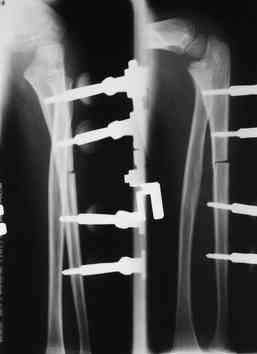

2 По снятии аппарата через 2 мес после операции рефрактура в месте остеотомии(на фоне активного ротационного движения)- под контролем ЭОП выполнен

интрамедуллярный остеосинтез TEN. Положение головки луча стабильное.

Последних снимков к сожалению нет. Больной иногородний, но скоро появится и снимки предоставим.